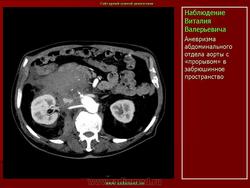

Аневризмы аорты. Ср, 22/06/2011 - 21:09 #1 Катенёв Валенти... Не на сайте Был на сайте: 7 лет 3 месяцев назад Зарегистрирован: 22.03.2008 - 22:15 Публикации: 54876 Продолжение. Приложения: Ср, 22/06/2011 - 21:19 #2 Катенёв Валенти... Не на сайте Был на сайте: 7 лет 3 месяцев назад Зарегистрирован: 22.03.2008 - 22:15 Публикации: 54876 Продолжение.Приложения: Втр, 05/07/2011 - 00:34 #3 Катенёв Валенти... Не на сайте Был на сайте: 7 лет 3 месяцев назад Зарегистрирован: 22.03.2008 - 22:15 Публикации: 54876 Продолжение.Приложения: Ср, 27/07/2011 - 03:58 #4 Катенёв Валенти... Не на сайте Был на сайте: 7 лет 3 месяцев назад Зарегистрирован: 22.03.2008 - 22:15 Публикации: 54876 Продолжение.Приложения: Ср, 05/10/2011 - 01:14 #5 Катенёв Валенти... Не на сайте Был на сайте: 7 лет 3 месяцев назад Зарегистрирован: 22.03.2008 - 22:15 Публикации: 54876 Расслоение аорты.Приложения: Втр, 06/12/2011 - 01:58 #6 Катенёв Валенти... Не на сайте Был на сайте: 7 лет 3 месяцев назад Зарегистрирован: 22.03.2008 - 22:15 Публикации: 54876 Расслоение аорты.Приложения: Чт, 15/12/2011 - 00:33 #7 Катенёв Валенти... Не на сайте Был на сайте: 7 лет 3 месяцев назад Зарегистрирован: 22.03.2008 - 22:15 Публикации: 54876 Продолжение.Приложения: Ср, 14/03/2012 - 22:41 #8 Катенёв Валенти... Не на сайте Был на сайте: 7 лет 3 месяцев назад Зарегистрирован: 22.03.2008 - 22:15 Публикации: 54876 Из литературных источников.Приложения: Втр, 17/04/2012 - 22:21 #9 Катенёв Валенти... Не на сайте Был на сайте: 7 лет 3 месяцев назад Зарегистрирован: 22.03.2008 - 22:15 Публикации: 54876 Аневризма аорты.Приложения: Ср, 18/04/2012 - 20:53 #10 Катенёв Валенти... Не на сайте Был на сайте: 7 лет 3 месяцев назад Зарегистрирован: 22.03.2008 - 22:15 Публикации: 54876 Аневризма аортыПриложения: Ср, 18/04/2012 - 20:57 #11 Катенёв Валенти... Не на сайте Был на сайте: 7 лет 3 месяцев назад Зарегистрирован: 22.03.2008 - 22:15 Публикации: 54876 Аневризма аортыПриложения: Вс, 03/06/2012 - 23:41 #12 Катенёв Валенти... Не на сайте Был на сайте: 7 лет 3 месяцев назад Зарегистрирован: 22.03.2008 - 22:15 Публикации: 54876 Аневризма аорты Приложения: Втр, 21/08/2012 - 18:16 #13 Катенёв Валенти... Не на сайте Был на сайте: 7 лет 3 месяцев назад Зарегистрирован: 22.03.2008 - 22:15 Публикации: 54876 Аневризма дуги аортыПриложения: Пнд, 03/06/2013 - 01:22 #14 Катенёв Валенти... Не на сайте Был на сайте: 7 лет 3 месяцев назад Зарегистрирован: 22.03.2008 - 22:15 Публикации: 54876 Аневризмы брюшной аортыПриложения: Чт, 27/06/2013 - 18:33 #15 Катенёв Валенти... Не на сайте Был на сайте: 7 лет 3 месяцев назад Зарегистрирован: 22.03.2008 - 22:15 Публикации: 54876 1. Аневризма грудной аорты. Приложения: Чт, 29/08/2013 - 21:12 #16 Катенёв Валенти... Не на сайте Был на сайте: 7 лет 3 месяцев назад Зарегистрирован: 22.03.2008 - 22:15 Публикации: 54876 Расслоение аорты ID: 12384 Aortic dissection with rupture into pericardium Dr Frank Gaillard - 19 Nov 2010 CTA demonstrates a Type A aortic dissection which has ruptured into the ... ID: 23726 Aortic dissection with rupture into the pericardial sac Dr J. Ray Ballinger - 5 Jul 2013 Aortic dissection is associated with hypertension, Marfan's syndrome and... Пнд, 07/10/2013 - 23:05 #17 Катенёв Валенти... Не на сайте Был на сайте: 7 лет 3 месяцев назад Зарегистрирован: 22.03.2008 - 22:15 Публикации: 54876 Расслоения аорты http://radiographics.rsna.org/content/23/suppl_1/S93.full Пт, 07/02/2014 - 10:38 #18 Катенёв Валенти... Не на сайте Был на сайте: 7 лет 3 месяцев назад Зарегистрирован: 22.03.2008 - 22:15 Публикации: 54876 Продолжение Приложения: Пт, 07/03/2014 - 10:28 #19 Катенёв Валенти... Не на сайте Был на сайте: 7 лет 3 месяцев назад Зарегистрирован: 22.03.2008 - 22:15 Публикации: 54876 Продолжение.Приложения: Чт, 07/08/2014 - 12:45 #20 Катенёв Валенти... Не на сайте Был на сайте: 7 лет 3 месяцев назад Зарегистрирован: 22.03.2008 - 22:15 Публикации: 54876 Наблюдение Tatarin Пнд, 22/09/2014 - 09:08 #21 Катенёв Валенти... Не на сайте Был на сайте: 7 лет 3 месяцев назад Зарегистрирован: 22.03.2008 - 22:15 Публикации: 54876 Наблюдение Tatarin Женщина 77 лет. Жалобы на боли в животе. Пальпируется образование в околопупочной области живота. Аневризмы брюшной аорты и обеих общих подвздошных артерий. Чт, 23/10/2014 - 11:40 #22 Катенёв Валенти... Не на сайте Был на сайте: 7 лет 3 месяцев назад Зарегистрирован: 22.03.2008 - 22:15 Публикации: 54876 Продолжение.Приложения: Вс, 13/08/2017 - 23:19 #23 Катенёв Валенти... Не на сайте Был на сайте: 7 лет 3 месяцев назад Зарегистрирован: 22.03.2008 - 22:15 Публикации: 54876 Продолжение. Приложения: Втр, 28/11/2017 - 08:34 #24 Катенёв Валенти... Не на сайте Был на сайте: 7 лет 3 месяцев назад Зарегистрирован: 22.03.2008 - 22:15 Публикации: 54876 Ao Aneurysm 1a Дата: 01/21/2006 Просмотров: 1387 Ao Aneurysm 1b Дата: 01/21/2006 Просмотров: 938 Ao Aneurysm 1c Дата: 01/21/2006 Просмотров: 934 Ao Aneurysm 2a Дата: 01/21/2006 Просмотров: 861 Ao Aneurysm 2b Дата: 01/21/2006 Просмотров: 740 Ao Aneurysm 2c Дата: 01/21/2006 Просмотров: 747 Ao Aneurysm 3a Дата: 01/21/2006 Просмотров: 736 Ao Aneurysm 3b Дата: 01/21/2006 Просмотров: 619 Ao Aneurysm 3c Дата: 01/21/2006 Просмотров: 709 Ao Aneurysm 4a Дата: 03/11/2006 Просмотров: 763 Ao Aneurysm 4b Дата: 03/11/2006 Просмотров: 703 Ao Aneurysm 5a Дата: 07/03/2006 Просмотров: 712 Ao Aneurysm 5b Дата: 07/03/2006 Просмотров: 664 Ao Aneurysm 5c Дата: 07/03/2006 Просмотров: 829 Сб, 30/12/2017 - 02:58 #25 Марина Сергеевна Не на сайте Был на сайте: 9 месяцев 1 неделя назад Зарегистрирован: 26.04.2011 - 11:56 Публикации: 996 Давно у меня картинки лежали, вот случай добавить в подборку. Аневризма дуги аорты, КТ-контроль после операции дебранчинга, следующим этапом будет установка протеза дуги аорты. Шунт магистальных сосудов "Carotid-to-subclavian bypass". Подробнее о таких операциях по ссылке. https://www.ncbi.nlm.nih.gov/pmc/articles/PMC3741848/ P.S. впереди от камер желудочов загрудинно в мягких тканях - те самые epicardial wires. https://radiomed.ru/cases/40958-chto-za-metallicheskie-niti-na-fone-pozvonochnika Приложения: "There is no teacher, who can teach us anything new. He just can help us to remember the things we always knew" (c) Enigma. Сб, 30/12/2017 - 07:21 #26 Катенёв Валенти... Не на сайте Был на сайте: 7 лет 3 месяцев назад Зарегистрирован: 22.03.2008 - 22:15 Публикации: 54876 Большое спасибо! Ср, 10/01/2018 - 19:17 #27 Катенёв Валенти... Не на сайте Был на сайте: 7 лет 3 месяцев назад Зарегистрирован: 22.03.2008 - 22:15 Публикации: 54876 Аневризмы аорты, фистулы и тромбы https://radiologykey.com/aortic-aneurysms-fistula-and-thrombus/ Ср, 10/01/2018 - 19:20 #28 Катенёв Валенти... Не на сайте Был на сайте: 7 лет 3 месяцев назад Зарегистрирован: 22.03.2008 - 22:15 Публикации: 54876 Аортальная травма https://radiologykey.com/traumatic-aortic-injury/ Вс, 18/02/2018 - 20:57 #29 Катенёв Валенти... Не на сайте Был на сайте: 7 лет 3 месяцев назад Зарегистрирован: 22.03.2008 - 22:15 Публикации: 54876 Диссекации. Ao Diss 1a Дата: 01/21/2006 Просмотров: 923 Ao Diss 1b Дата: 01/21/2006 Просмотров: 613 Ao Diss 1c Дата: 01/21/2006 Просмотров: 730 Ao Diss 2a Дата: 31.12.2004 Просмотров: 699 Ao Diss 2b Дата: 31.12.2004 Просмотров: 586 Ao Diss 3 Дата: 26.02.2006 Просмотров: 606 Ao Diss 4a до Дата: 31.12.2004 Просмотров: 574 Ao Diss 4b IMH Дата: 31.12.2004 Просмотров: 565 Ao diss 4c Дата: 31.12.2004 Просмотров: 540 Сб, 10/03/2018 - 15:41 #30 Катенёв Валенти... Не на сайте Был на сайте: 7 лет 3 месяцев назад Зарегистрирован: 22.03.2008 - 22:15 Публикации: 54876 http://www.nejm.org/doi/full/10.1056/NEJMicm1506911 Приложения: